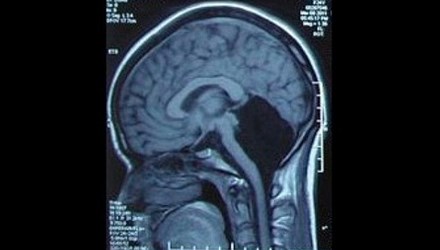

Old  Default Lạ kỳ cô gái mất nửa não bộ, vẫn sống bình thường

Cô gái đã lập gia đình và có một con gái. Các bác sỹ đã hết sức ngạc nhiên khi phát hiện cô không có tiểu não tức là thiếu một nửa não bộ mà vẫn có thể sống bình thường.

Một phụ nữ, 24 tuổi, ở tỉnh Quảng Đông, Trung Quốc phải nhập viện vì cảm thấy chóng mặt và buồn nôn. Sau khi chụp não, các bác sỹ của bệnh viện quân đội Quảng Đông hết sức ngạc nhiên khi phát hiện cô không có tiểu não (phần màu đen trong ảnh), tức là thiếu một nửa não bộ mà vẫn có thể sống bình thường.

Tiểu não nằm ở trung tâm hộp sọ, chứa khoảng một nửa số nơ ron thần kinh, khu vực chỉ huy việc cân bằng cơ thể, chạy nhảy, đá bóng và ngôn ngữ.

Do thiếu tiểu não nên đến 6 tuổi cô mới biết nói, 7 tuổi mới biết đi. Các cuộc kiểm tra cho thấy, cô có thể hiểu được các từ, nhưng gặp khó khăn khi phát âm, giọng của cô hơi run run và phát âm không được chuẩn.

Hiện cô đã có gia đình và có một con gái. Rất may cô bé có bộ não bình thường. Đây là một trong số 9 người trên thế giới mắc căn bệnh hiếm gặp này. Các bác sỹ tin rằng, các chức năng của tiểu não của cô có thể đã được thay thế bởi vỏ não.